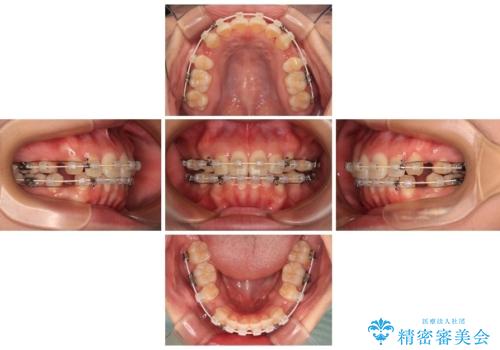

- 全体的なデコボコと口元の突出感を改善したいとのことで来院された患者様です。

このままデコボコを整えるとさらに突出感が増すため、上下左右の第一小臼歯を抜歯し、ワイヤー装置にて矯正しました。

結婚式で途中装置を外した時期がありましたが、2年で治療を終えることができました。